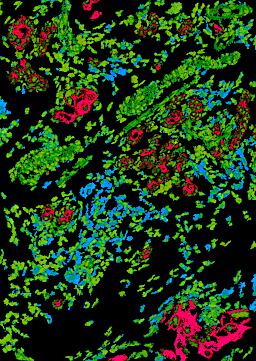

Pancreatic ductal adenocarcinoma is a lethal disease with limited treatment options and poor survival. We studied 83 spatial samples from 31 patients (11 treatment-naïve and 20 treated) using single-cell/nucleus RNA sequencing, bulk-proteogenomics, spatial transcriptomics and cellular imaging. Subpopulations of tumor cells exhibited signatures of proliferation, KRAS signaling, cell stress and epithelial-to-mesenchymal transition. Mapping mutations and copy number events distinguished tumor populations from normal and transitional cells, including acinar-to-ductal metaplasia and pancreatic intraepithelial neoplasia. Pathology-assisted deconvolution of spatial transcriptomic data identified tumor and transitional subpopulations with distinct histological features. We showed coordinated expression of TIGIT in exhausted and regulatory T cells and Nectin in tumor cells. Chemo-resistant samples contain a threefold enrichment of inflammatory cancer-associated fibroblasts that upregulate metallothioneins. Our study reveals a deeper understanding of the intricate substructure of pancreatic ductal adenocarcinoma tumors that could help improve therapy for patients with this disease.